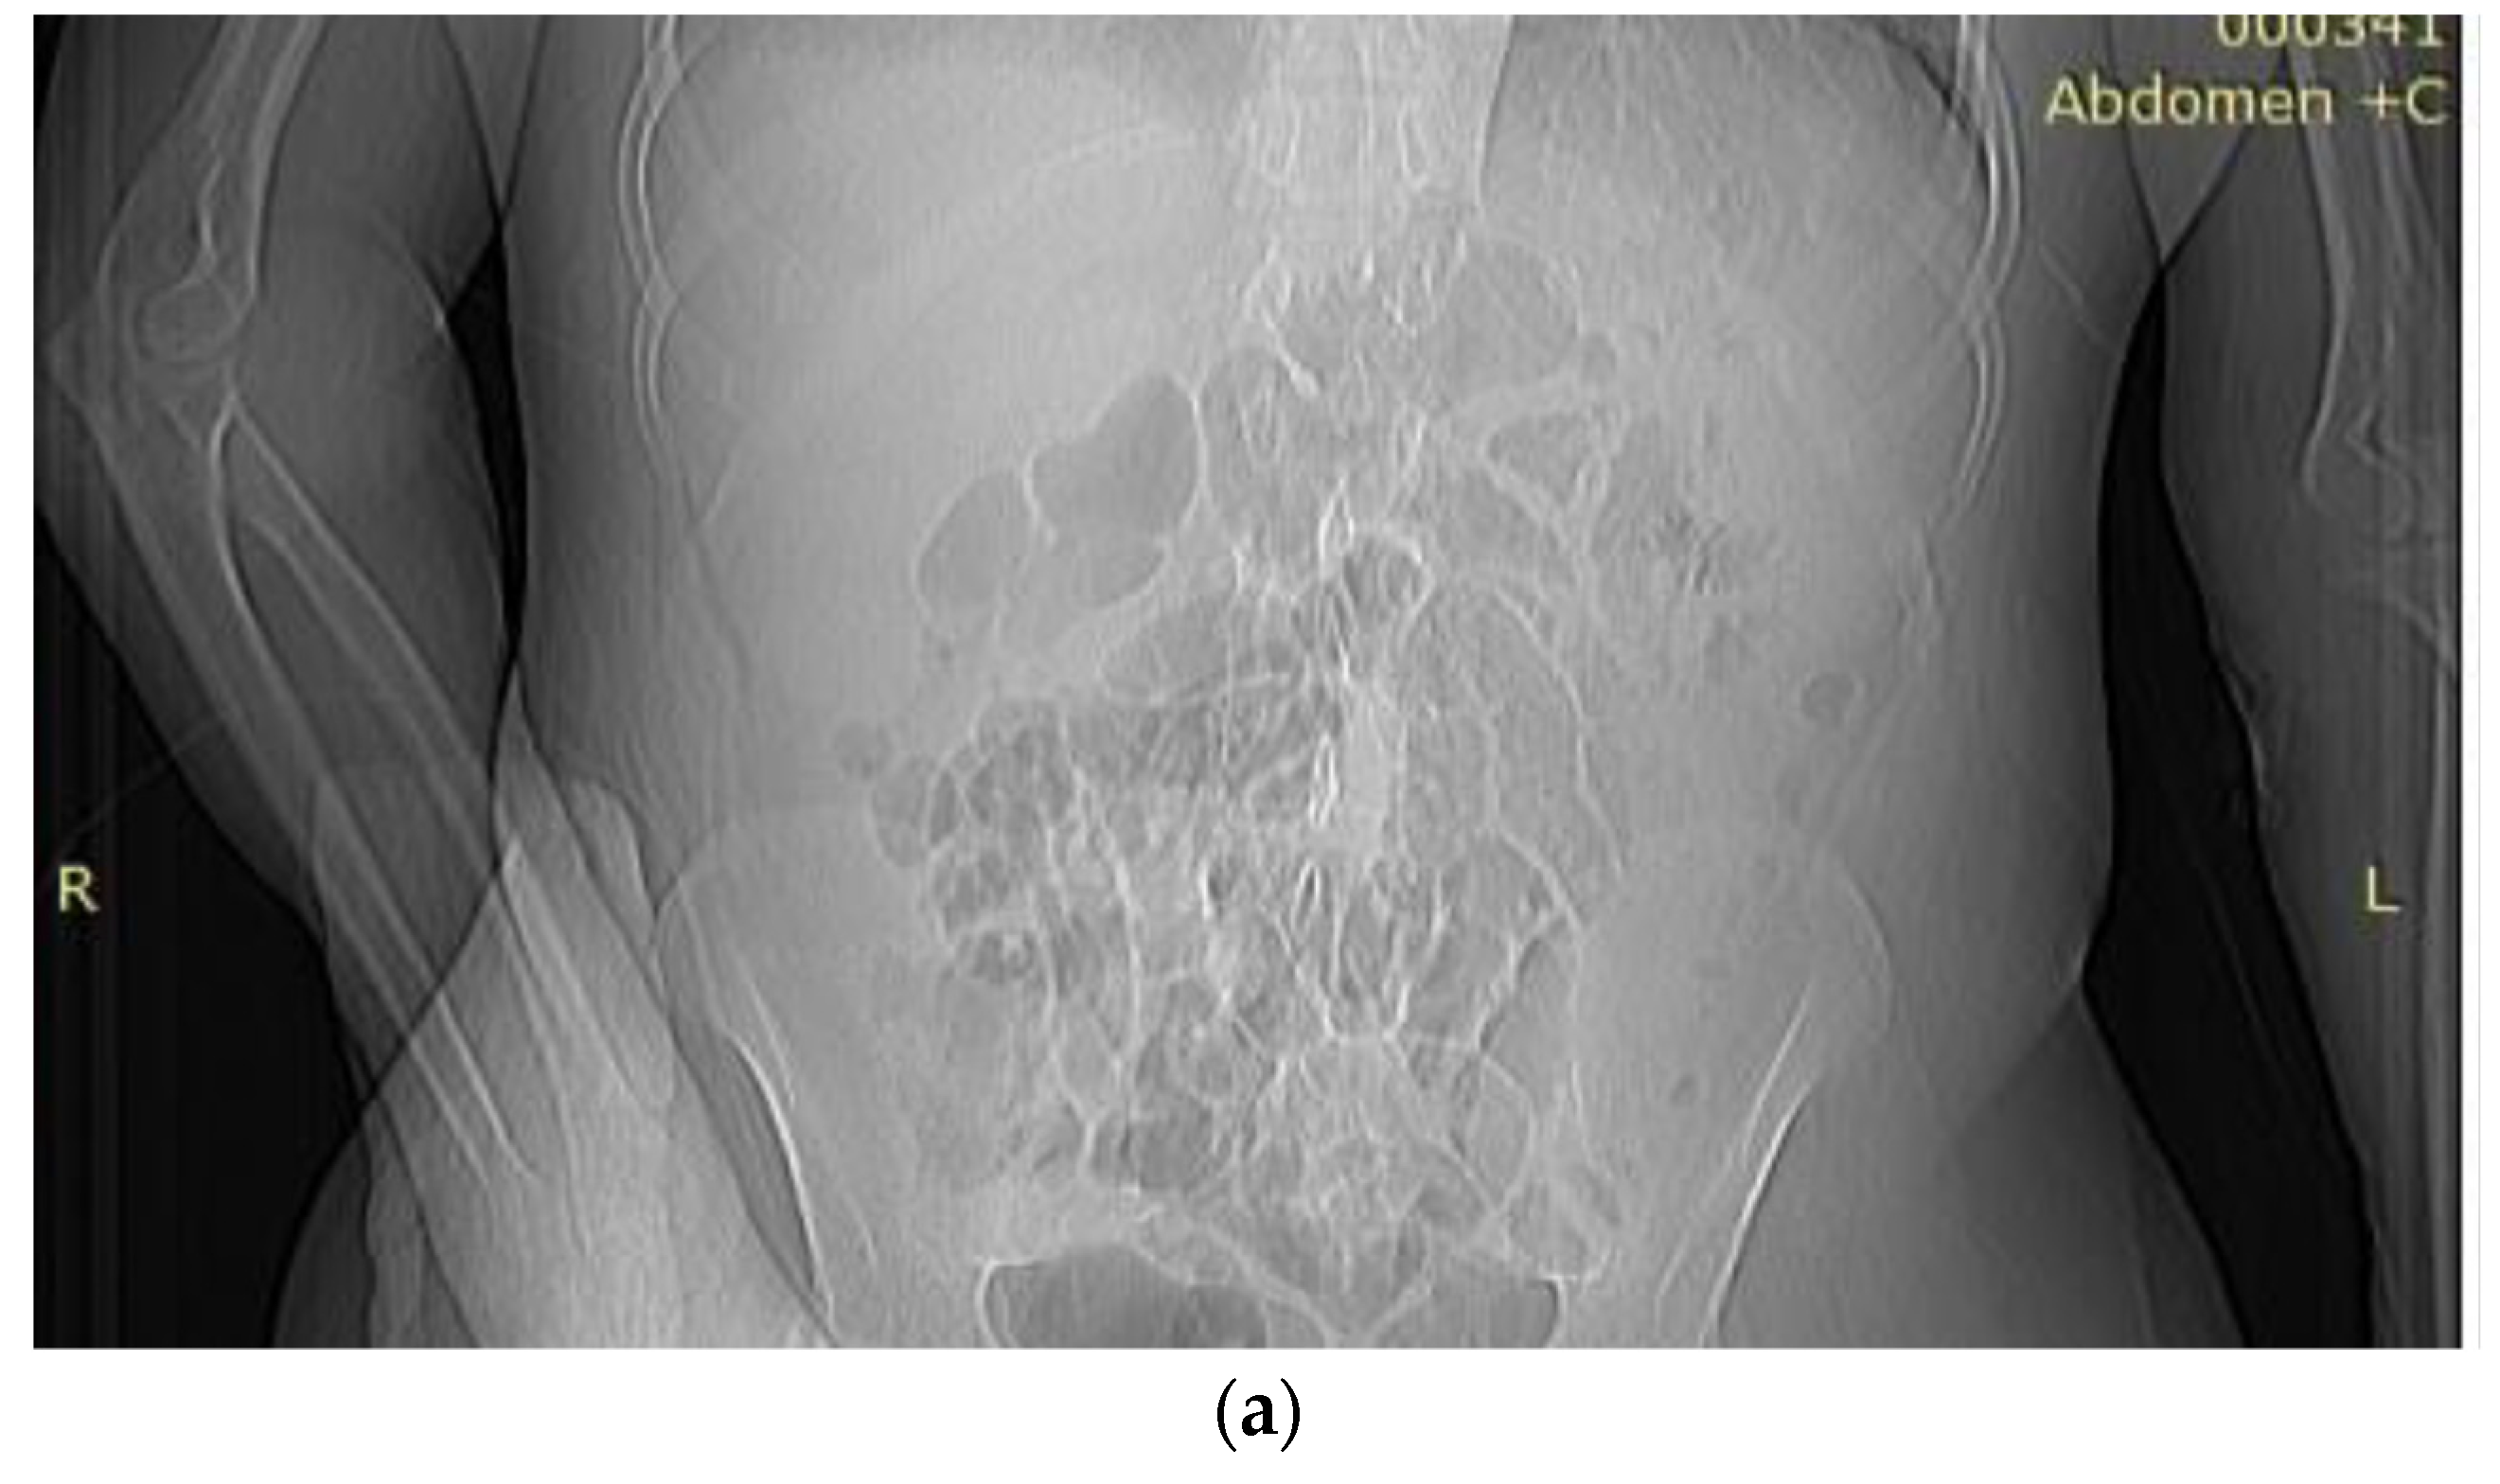

- Pale skin and mucous membranes, jaundice, petechiae on the right forearm, livedo reticularis on the left lower limb, bilateral onycholysis (Figure 1a,b)